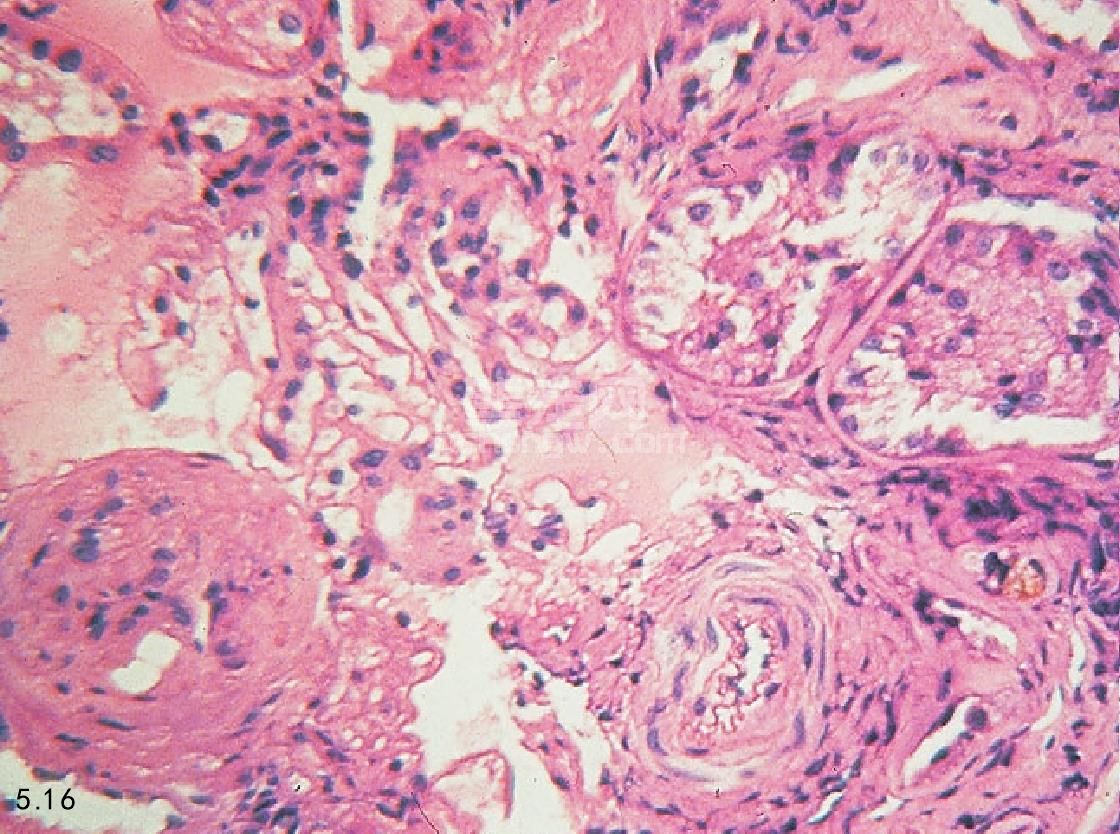

诊断 根据临床调查、身体检查(见以上部分)和实验室检查结果来确定是否患有CRF。典型的检查结果包括红细胞正常的色素性贫血、淋巴细胞减少、氮质血症、高磷酸盐血症和负离子升高引起的代谢性酸中毒。脂肪酶和淀粉酶比正常升高2.5~3倍,但不会出现胰腺炎。尿液检查显示为等渗尿、轻度蛋白尿(除非疾病过程特殊,涉及到了肾小球)和良性尿沉积物。在这些情况下,可以观察到管型,它们直径比较宽。在进行X线和超声诊断时,肾脏的大小、形状和密度会有异常。肾脏组织活检显示,在肾血管球硬化症和单核性间隙性渗透的纤维化时,肾小球和肾小管有不同程度的萎缩(图5.15和图5.16)。在表述氮质血症的症状和程度时会有很大差别。

图5.15和图5.16 犬慢性肾衰竭肾脏的组织病理学。图5.15肾血管球硬化症和单核性间隙性渗透病变。图5.16肾小管萎缩和间隙纤维化。